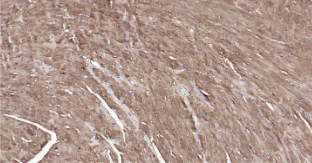

Immunohistochemical analysis of paraffin embedded mouse heart tissue slide using IHC0215M (Mouse S100A1 IHC Kit).